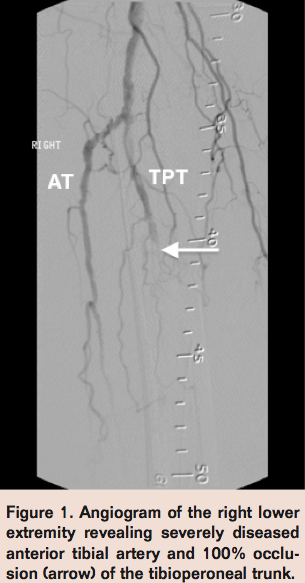

An 82-year-old male with history of hypertension, dyslipidemia, and chronic venous insufficiency presented with a nonhealing right heel ulcer and critical limb ischemia (CLI). Physical examination was unremarkable except for a well-demarcated 1-cm erythematous ulceration at the right heel without drainage and mild tenderness on palpation. Pedal pulses were nonpalpable in the right foot, but the dorsalis pedis pulse was present on Doppler. Ankle Brachial Index (ABI) measurement revealed an abnormal result of 0.65 in the right lower extremity compared to 0.95 in the left. Subsequent diagnostic peripheral angiography confirmed a severely diseased anterior tibial (AT) artery with distal tibioperoneal trunk (TPT) 100%occlusion (Figure 1) with faint reconstitution of the peroneal and posterior tibial (PT) arteries via collaterals.